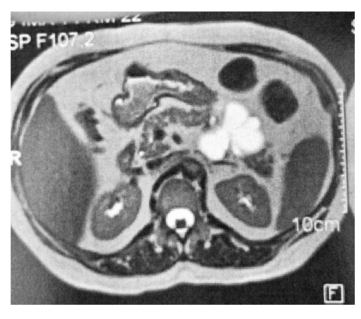

Um homem de 52 anos de idade apresenta a lesão pancreática assintomática mostrada a seguir.

Com base nesse caso hipotético, é correto afirmar que a lesão menos provável com relação ao diagnóstico final é o(a)